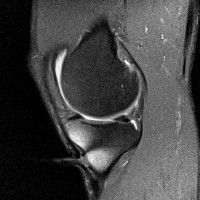

무릎 mri 간단히 봐주실 수 있으시나요 ㅠㅠ

안녕하세요 8년전 십자인대 수술하고 최근 무리한 운동에 무릎 불편감이 생겨서

mri 찍었습니다.

진단결과는 첫 찍은 병원에서 활액막염 이라는 진단을 받았습니다. 혹시 봐주실 수 있으실까요?

올라온 MRI가 단편적이라서 정확한 진단에 어려움이 있지만 십자인대에는 큰 이상이 있지는 않은것 같으며, 무릎관절내 물이 있는 것으로 보아 활액막염의 진단이 맞을 것 같습니다.

하지만 단편적인 영상이기 때문에 촬영병원에서 정확한 판독지 등을 받으시는 것이 좋겠습니다.